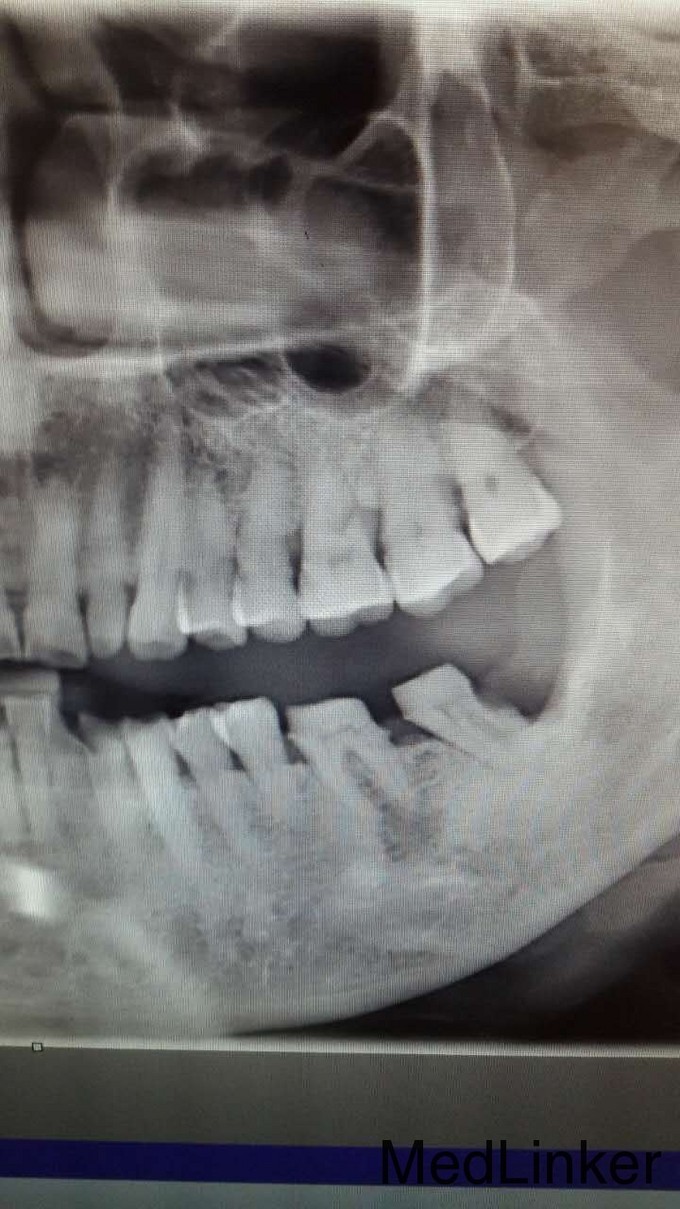

邓超 男 55 左侧固定义齿咬合痛一月

根管治疗桩核固定义齿修复